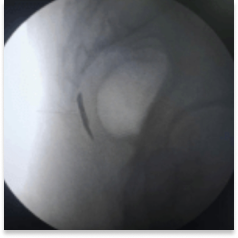

This procedure is performed with the patient in a prone position on the Operating table. Some practitioners like to prepare patients with laxatives the night before. With fluoroscopic guidance, a thin spinal needle is advanced through the sacrococcygeal hiatus. Needle placement is confirmed and dye spread is checked under fluoroscopy. Medication is delivered at the site of the Ganglion of Impar. This helps in blocking the sacrococcygeal plexus of nerves.

Intraop fluoroscopy image of contrast dye injection for confirmation of placement of needle

Intraop fluoroscopy video

of contrast dye injection for confirmation of placement of needle